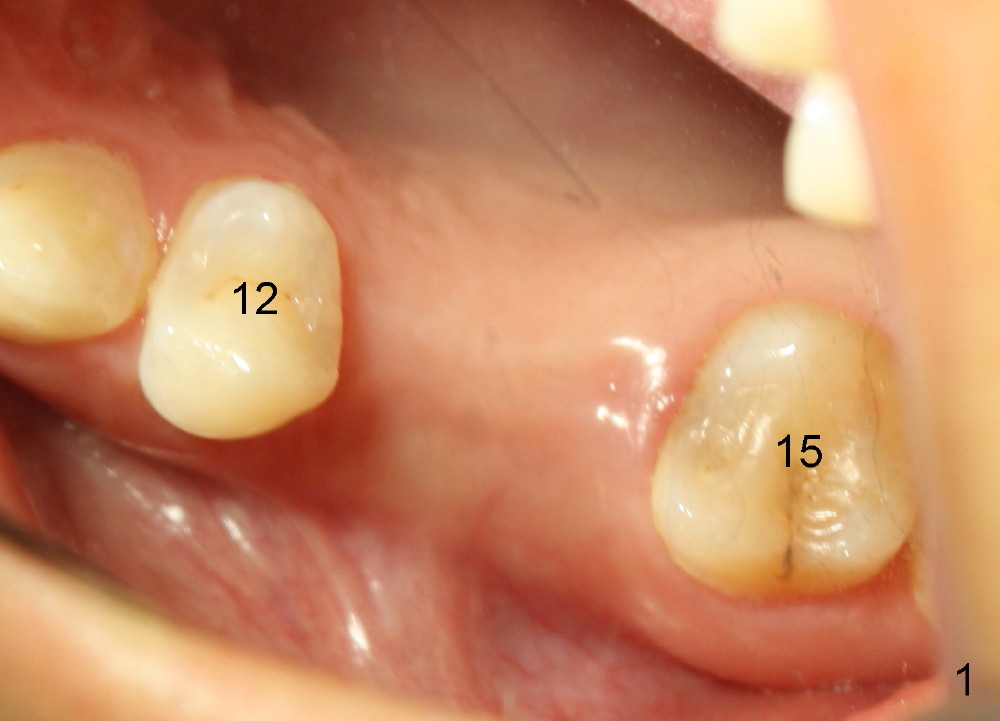

The patient returns for #13,14 implant placement. The ridge appears to be wide buccolingually (Fig.1 mirror view). A 4 mm tissue punch is used for access at the sites of #13 and 14. Osteotomy is initiated by using 3 mm trephine bur at the depth of 4 mm at both sites; 2 mm pilot drill is used to continue osteotomy at 8 mm deep at the site of #13. Sinus lift is accomplished by using tapered osteotomes 2,3 mm 6 mm deep, followed by 4.5x11 mm tap (Fig.2 T); 2 mm pilot drill (P) is reinserted into #13 osteotomy site with inadvertently penetrating the sinus floor. When the tap is removed from the site of #14, the sinus membrane is also found to be perforated. The sinus membrane at both sites is repaired by insertion of collagen dressing before bone graft. A 4x11 mm one-piece implant is placed at the site of #13 slowly hoping that it does not re-perforate the sinus membrane (Fig.3 O). Due to limited restorative height, the abutment portion of the one-piece is expected to be trimmed (Fig.4 O). In case of implant complication or failure, the implant may be difficult to be removed. Therefore the implant at the site of #14 is two piece one (Fig.4,5 I/A, 5x11 and 4x3 mm, respectively). The insertion torques for #13 and 14 are 35/40 and >60 Ncm. Immediate provisionals are canceled mainly because of patient's inability to open wide for long. Perio dressing is placed instead after adjustment of the height of the abutments. The patient experiences one episode of light nasal hemorrhage a few hours postop. Although the patient takes Amoxicillin for 1 week periop, the implant at the site of #13 dislodges 1 months postop (Fig.5). Immediate re-placement with a larger 2 piece one is canceled because of mild infection mesiobuccal to the implant at the site of #14 (Fig.6 >). Exploration around the latter implant reveals possible thread exposure in a small area. After copious irrigation with normal saline, Arestin is placed. Two months post exfoliation, the site is re-entered (Fig.7,8). There is a lingual defect. Osteotomy is initiated as buccal as possible. A 4.5x11 mm tapered tap penetrates the sinus floor without tearing the membrane (Fig.9). The same-sized implant is placed (25/30 Ncm) with sinus lift (Fig.10 *). The lingual defect is bone grafted. There is dehiscence lingually 7 days postop (Fig.11). Impression for final restoration is taken 1.5 months postop because of pending wedding. The crown has been in function for 2.5 months.